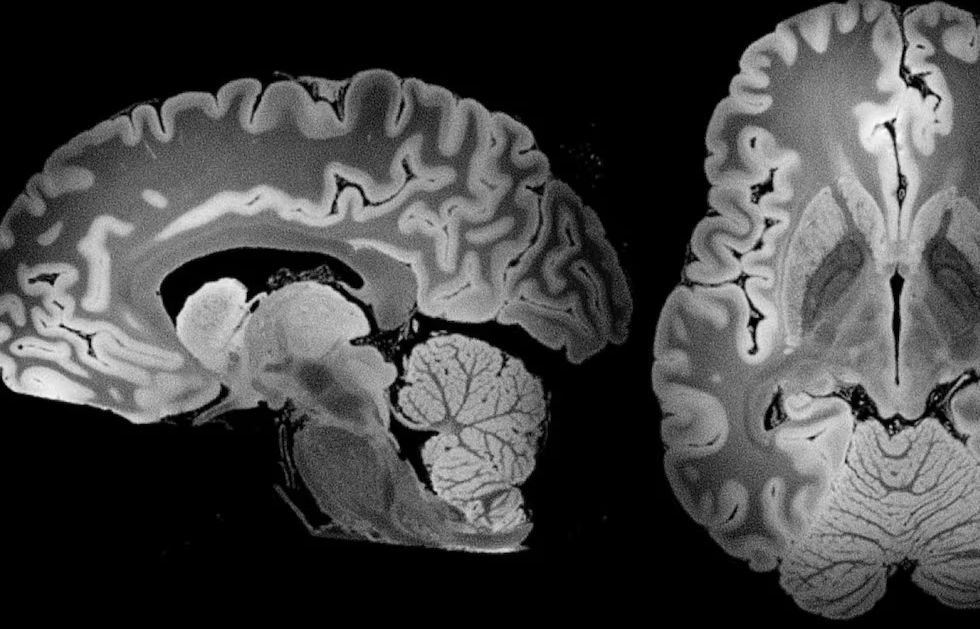

Ante este contexto, no es de extrañar que portemos plástico en nuestro organismo. Diferentes investigaciones los han detectado en la sangre, en los pulmones, en las placentas, en los testículos, en los riñones y en el hígado, entre otras. Ahora, un estudio (pendiente de revisión por pares) de la Universidad de Nuevo México -UNM- evidenció una alarmante concentración de partículas plásticas en el cerebro humano.

Los investigadores estudiaron muestras del tejido de cerebros, riñones e hígados de 92 individuos sometidos a autopsia en 2016 y 2024. Descubrieron que la concentración plástica promedio en el cerebro es de “4,800 microgramos por gramo de tejido”, el doble que las muestras del 2016, detalla Mathew Campen, coautor del estudio,

Además, revelaron que el cerebro atrae partículas más pequeñas, mientras que las más grandes van a órganos como el hígado o los riñones, según la prepublicación las muestras cerebrales tenían entre un 7% y un 30% más plástico que los análisis de riñones. Campen advierte que estas partículas parecen atravesar la barrera hematoencefálica y acumularse en el cerebro, lo que podría alterar funciones neurológicas.